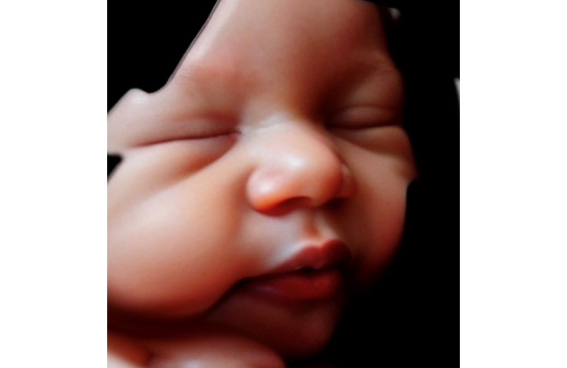

Se puede realizar en cualquier momento de la gestación aunque preferimos realizarla a partir de la semana 28 porque por la madurez fetal realiza más gestos como sacar la lengua, reír, bostezar , etc y además con la incorporación de la Inteligencia Artificial a la ecografía 5D esta se convierte en una imagen hiperrealista , es como será tu bebé cuando nazca.

Para que tengas un recuerdo que podrás compartir con él/ella , en el futuro te podrás descargar todas las fotos y pequeños videos en tu móvil a través de un QR en el momento, o fotos impresas y video en una memoria USB, si deseas además una imagen hiperrealista incluye una foto y un vídeo pequeño que se envía al día siguiente a tu correo electrónico.